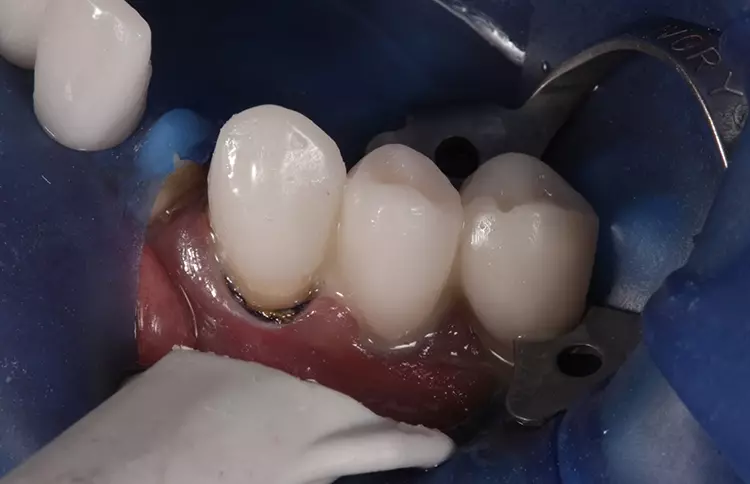

In den darauffolgenden Sitzungen wurden die Zähne 35, 37, 44 und 46 für die definitive Versorgung mit Presskeramikteilkronen versorgt sowie verschraubte Implantatkronen 036 und 045 eingegliedert (Abb. 11). Nach anschließender Präparation für die definitive Versorgung im Oberkieferseitenzahnbereich der Zähne 14 bis 16 sowie 24 bis 26 wurden Presskeramikteilkronen eingegliedert (Abb. 12).